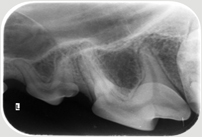

Neben der allgemeinen Untersuchung und der Untersuchung der Zahntaschen mittels Parodontalsonde sind ZAHNRÖNTGEN unumgänglich für eine komplette Diagnostik von Parodontalerkrankungen und bei Zahnresorptionen vor allem bei der Katze (FORL). Dabei werden spezielle Techniken mit Dentalfilmen wie beim Menschen verwendet.

In der Kleintier-Ordination Mittertreffling wird eine moderne digitale Entwicklung verwendet, die die Strahlenbelastung für Ihr Tier verringert. Ohne Zahnröntgen wird das Ausmaß des Knochenverlustes oft unterschätzt und bei der Katze viele Zahnresorptionen übersehen oder unterschätzt. Zudem ist bei einer wie in der Tier-Zahnheilkunde in einer Sitzung durchgeführten Wurzelbehandlung (Endodontie) eine Kontrolle durch Zahnröntgen unbedingt notwendig. Selbst Tumoren können sehr gut erkannt werden und auch die Kontrolle einer Zahnbewegung (Orthodontie) sollte durch Zahnröntgen erfolgen.

Katze mit hochgradiger RL Tumor im Unterkiefer Intraorales Zahnröntgen bei Tumor im Unterkiefer